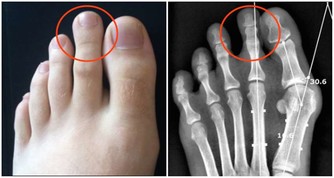

治療風濕:生薑具有特殊的驅寒祛風的功效,風濕患者每天晚上持續泡腳半小時,能夠有效地減輕病症。用木桶泡腳,泡過小腿,能夠緩解風濕關節炎。